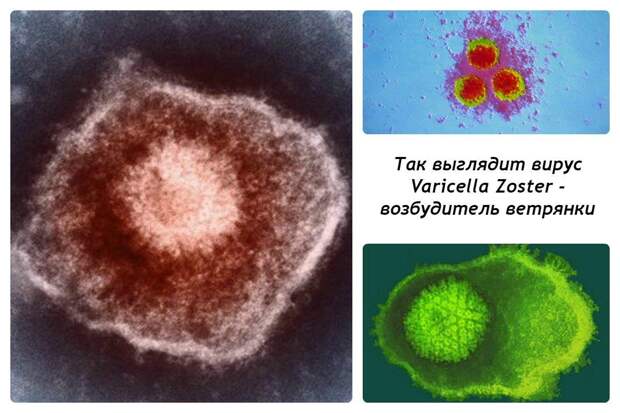

Медицинские снимки и изображения опоясывающего герпес вируса

Раздел: Фотодневник открытий